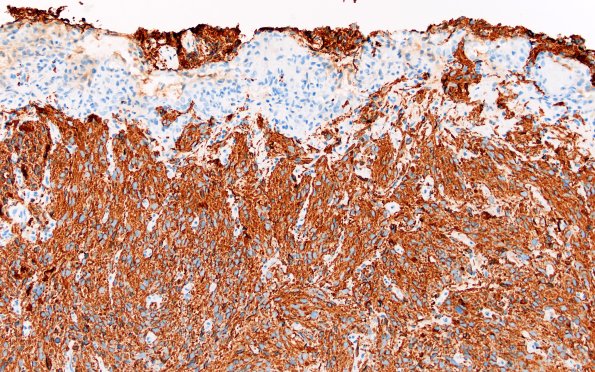

1C3,4 Proliferated vasculature stands out against the labeled tumor cells (GFAP IHC)